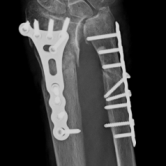

Röntgenbilder